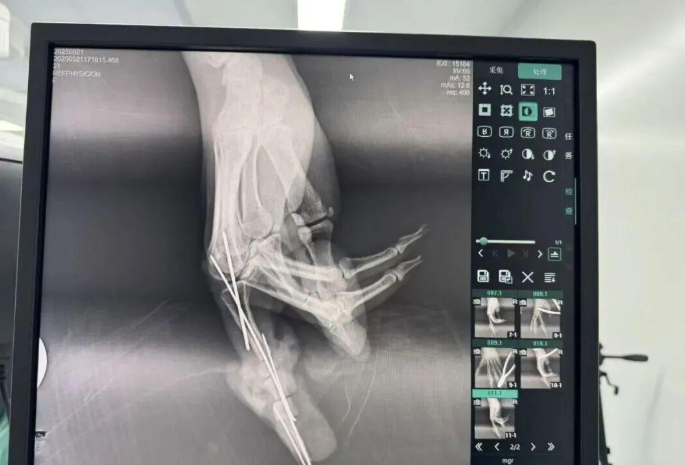

為確保手術(shù)成功,楊志主任特別聯(lián)合劉金海主任組成多手術(shù)組協(xié)作團(tuán)隊,充分發(fā)揮梯隊配合優(yōu)勢,反復(fù)研討后確定了“組合式”手指再造方案:利用右足踇趾的皮瓣、末節(jié)甲床及部分趾骨,聯(lián)合第二趾的趾間關(guān)節(jié),再取部分髂骨進(jìn)行精確植骨,將這些組織精密拼裝,重建一個兼具良好外形和功能的新示指。

手術(shù)當(dāng)天,多手術(shù)組梯隊配合的優(yōu)勢得到充分體現(xiàn)。無影燈下,楊志主任與團(tuán)隊各司其職、緊密配合,一場漫長的生命接力就此展開。在放大40倍的專業(yè)手術(shù)顯微鏡下,醫(yī)生們開始了精細(xì)操作。楊志主任在術(shù)后解釋道:“患者需要吻合的血管直徑僅0.5-1.0毫米左右,末節(jié)手指的毛細(xì)血管更是細(xì)如發(fā)絲。我們必須將移植組織與手部的血管、神經(jīng)、肌腱進(jìn)行精準(zhǔn)吻合,確保移植組織通血成活。這不僅要求醫(yī)生有扎實的顯微外科技術(shù),還要具備專業(yè)的整形外科審美能力,才能讓再造的指尖既好用又好看?!?/p>

手術(shù)中團(tuán)隊發(fā)現(xiàn),由于葉女士患有多年的內(nèi)分泌系統(tǒng)疾病,其血管質(zhì)量不佳,存在血管內(nèi)膜分層、動脈頑固性痙攣等挑戰(zhàn)。面對這一情況,團(tuán)隊及時啟動應(yīng)急預(yù)案。“每一根血管的吻合都不能有絲毫偏差,稍有不慎就可能出現(xiàn)血管內(nèi)血流不暢,從而導(dǎo)致移植組織壞死?!睏钪局魅窝a(bǔ)充道。